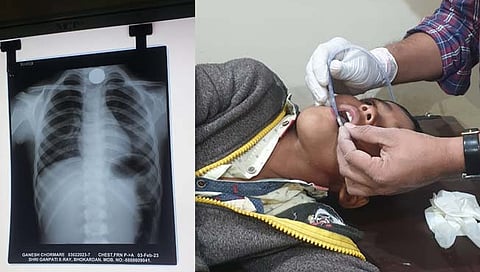

गणेशने ५ रुपयाचे नाणे गिळल्याने गणेशला त्रास होउ लागला. ते पाहून त्याच्या पालकांनी त्याला भोकरदन येथील सिल्लोड रस्त्यावरील शाश्वत हॉस्पिटल येथे नेले. तोपर्यंत गणेशला श्वास घेण्यास त्रास होणे, वारंवार उलट्या होणे यासारखा त्रास होउ लागला. दरम्यान भोकरदन येथील डॉ. विजय साबळे व त्यांच्या टीमने एक्स रे करून नाणे अडकल्याची जागा निश्चित केली. यानंतर कोणतीही शस्त्रक्रिया न करता फोलिज कॅथेटरच्या मदतीने ५ रुपयांचे नाणे बाहेर काढण्यात डॉक्टरांनी नाणे काढले.

५ रुपयांचे नाणे गिळलेल्या १२ वर्षांच्या मुलावर कोणतीही शस्त्रक्रिया न करता फोलिज कॅथेटरच्या साह्याने त्याचे प्राण वाचवण्यात भोकरदनच्या डॉक्टरांना यश आले. अन्न आणि श्वास नलिकेत अडकलेले नाणे काढण्यास अनेक खासगी रुग्णालयात नकार दिला होता. अखेरचा पर्याय म्हणून मुलास भोकरदन येथील शाश्वत हॉस्पिटलमध्ये दाखल करण्यात आले होते. यानंतर डॉ. विजय साबळे यांनी अर्ध्या तासाच्या अथक प्रयत्नातून आपले कसब लावून मुलास जीवनदान दिले. यामुळे पालकांनी डॉक्टरांचे आभार मानले.